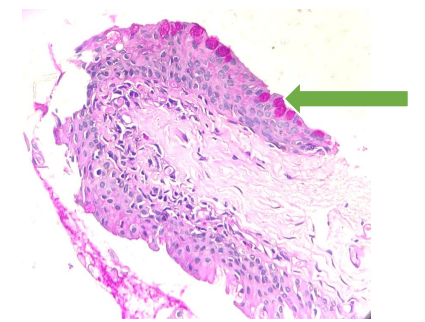

Goblet cells-stained magenta pink (arrow) with Periodic Acid Schiff-Diastase stain (magnification 40X)